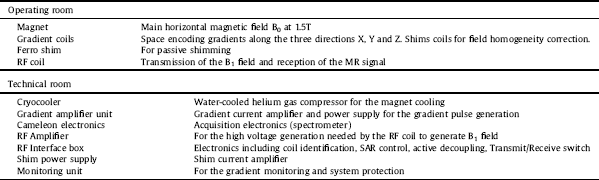

The MR scanner is designed to be fully compatible with the PET module. The magnet integrates a new technology bringing together a very compact design with a cryogen-free magnet at the most widely available clinical field of 1.5T. The limited axial dimension reduces the claustrophobic effects for the patient and gives the possibility of PET bolus injection under control, the arms outside of the magnet. Fig. 4 represents the actual dimension of the magnet produced by SSI, Superconducting Systems Inc., U.S.A. The magnet coil is cooled with a cryocooler that takes a minimum amount of space near the magnet and allows the system to work without any cryogenic fluids (no liquid helium, no liquid nitrogen). Eighteen days are needed to cool down the magnet before energizing it. As a result, the simpler safety requirements reduce the cost and the installation complexity.

Fig. 4 Schematic drawing of the MR magnet.

The magnet has been temporarily installed at RS2D (Strasbourg, France) for testing. A dedicated Faraday cage was built and installed around it. A description of the general properties of the MR component for the parts in the operating room and in the technical room is given in Table 2.

Table 2 MR System components.

In addition to the measurement of the static B0 and of the magnetic field gradient strengths, imaging measurements were carried out on a standard MR phantom consisting of a PMMA cube (135 × 135 × 135 mm3) inside a cylinder (200 mm diameter and 160 mm length) filled with a preparation composed of 5 l of demineralized water, 18 g of NaCl and 6.25 g of CuSO4.

The selected RF coil is designed in two layers: the outer layer is a dedicated transmit-only, quadrature birdcage coil and the inner part is a receive-only, 8-channel phased array coil. Since the delivery date for this coil is December 2017, two other coils were used for testing the sequences to be implemented on the MR Scanner. The second one is an eight-channel degenerate birdcage coil for transmission and detection, manufactured using non-magnetic, fixed and variable capacitors located outside the PET field-of-view. The coils support frame is 3D printed on a polycarbonate substrate. The third coil is a quadrature birdcage coil built with copper tape on a PMMA cylinder tuned for the 1.5 T magnet.